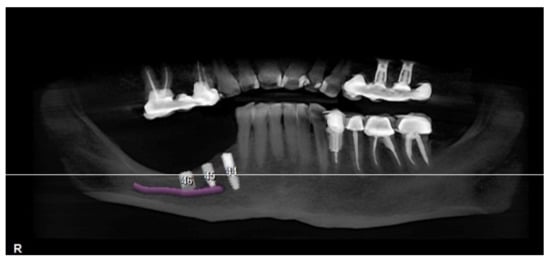

A CBCT scan was made with an initial setup for guided surgery, demonstrating a bone height less than 4 mm from the mandibular canal (Figure 2 and Figure 3a,b).

Figure 2.

Panoramic radiograph showing the implant planning and nerve position.